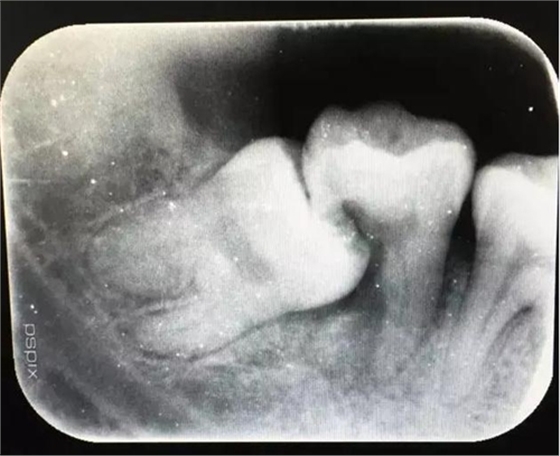

圖2.術(shù)前的x線根尖片影像檢查:47遠中牙根吸收。